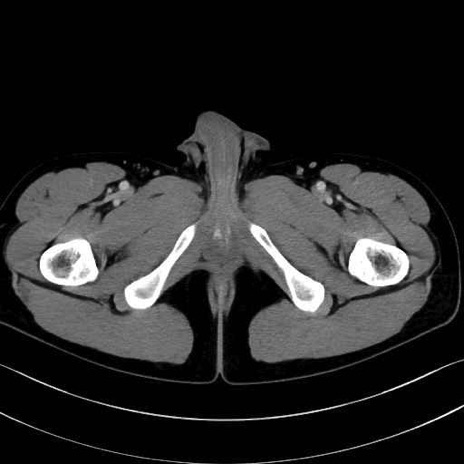

梨状筋(piriformis muscle) のCT画像の解剖

梨状筋 (Piriformis)

内閉鎖筋 (Obturator internus)

外閉鎖筋 (Obturator externus)